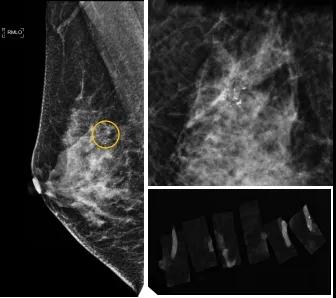

46歲的某女士在西安國際醫(yī)學中心醫(yī)院體檢時,行乳腺X線攝影(俗稱鉬靶)發(fā)現(xiàn)右乳可疑簇狀鈣化,分布范圍不到1厘米,臨床觸不到,超聲很難發(fā)現(xiàn),但是這種鈣化風險比較高,依據(jù)國際BI-RADS指南需要明確病理!

西安國際醫(yī)學中心醫(yī)院影像診療中心陳寶瑩副主任帶領的團隊,采用全數(shù)字化乳腺X線三維立體定位系統(tǒng)可實施。這個團隊的成員大部分來自知名三甲醫(yī)院,有著十余年影像引導下乳腺介入診療的經(jīng)驗,X線引導穿刺定位和活檢例數(shù)居西北前列。為減少患者創(chuàng)傷,在詳細判讀了患者資料,并與患者及甲乳外科劉曉敏主任充分溝通的基礎上,團隊確定采用全數(shù)字化乳腺X線三維立體定位系統(tǒng)下實施粗針活檢。

當天,乳腺X線三維立體定位系統(tǒng)清晰顯示出了所有鈣化。為了獲取充足的組織量,保證病理診斷的準確性,團隊選用14G穿刺針并多點、多角度取材,組織取出后,又立即在高清標本攝影系統(tǒng)中進行投照,從而確定了取出組織中具有足夠的可疑鈣化。整個過程患者無任何不適,活檢結束后即回家觀察。